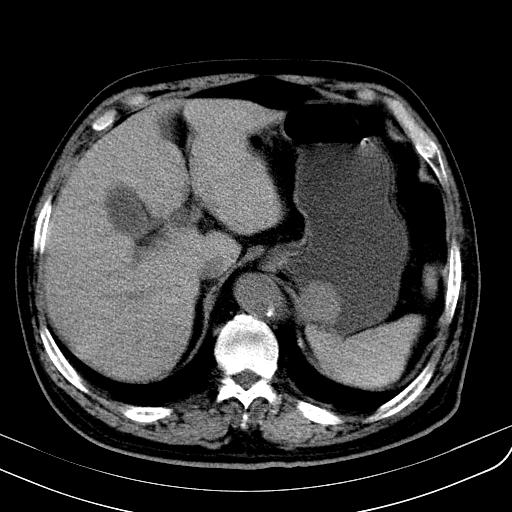

胃底靠近胃大弯处可见一圆形软组织影,直径为3.45cm,ct值约为30.1hu

边缘光滑,密度均匀,良性占位,首先考虑平滑肌瘤。

边缘光滑,密度均匀,良性占位,首先考虑平滑肌瘤。其实平滑肌瘤也是间质瘤的一种